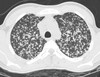

What are the radiographic appearances of Acute Respiratory Distress Syndrome (ARDS)?

Bilateral, patchy, ill-defined areas of consolidation ## Footnote Similar to PE (without the large heart)

184

# What pathology is this describing? -Breakdown of lung parenchyma -Substantial leakage of fluid/cells into interstitial/alveolar spaces -Low levels of O2 in blood -Severe respiratory impairment

Acute Respiratory Distress Syndrome (ARDS)

185

What pathology is seen here?